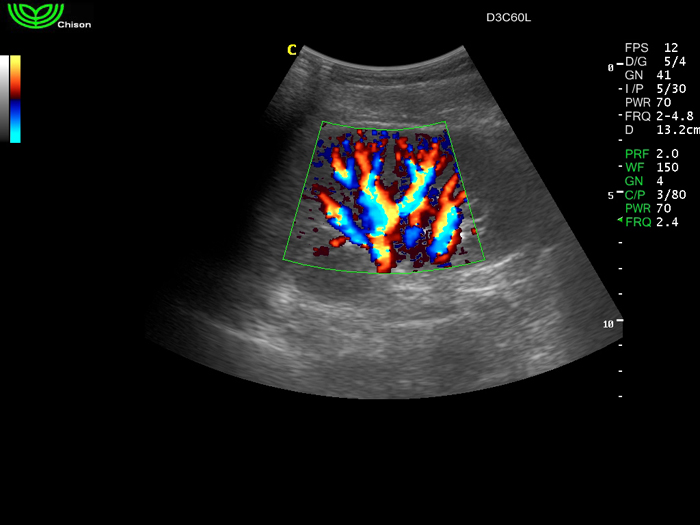

D3C60L 3.5МГц, конвексный.

2.0МГц - 5.8 МГц. Применения: абдомиальное обследование, акушерство, гинекология, обследование районной блокады нерва, осуществление и управление биопсией. |